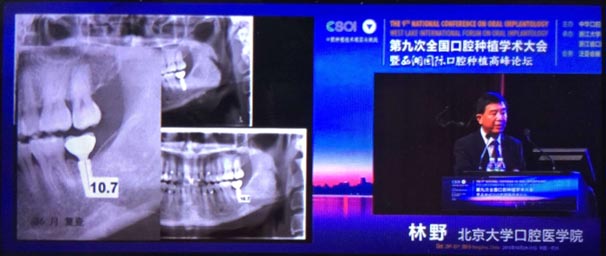

2015年10月29日第九次全國(guó)口腔種植學(xué)術(shù)大會(huì)暨“西湖國(guó)際”口腔種植高峰論壇在浙江省人民大會(huì)堂隆重開(kāi)幕。這是中華口腔種植專(zhuān)業(yè)委員會(huì)主辦的兩年一度的全國(guó)性學(xué)術(shù)會(huì)議,代表了中國(guó)口腔種植學(xué)發(fā)展的水平和方向。

會(huì)議期間國(guó)內(nèi)知名口腔專(zhuān)家針對(duì)當(dāng)前口腔種植領(lǐng)域熱點(diǎn)進(jìn)行了精彩的學(xué)術(shù)演講。其中北京大學(xué)口腔醫(yī)學(xué)院林野教授的演講主題是“種植體設(shè)計(jì)及臨床意義”。

威高演講中林野教授對(duì)國(guó)產(chǎn)品牌WEGO牙種植體系統(tǒng)的設(shè)計(jì)和臨床表現(xiàn)表示肯定,向在座觀眾展示了WEGO牙種植體系統(tǒng)的臨床病例。病例對(duì)76枚WEGO牙種植體進(jìn)行了平均21個(gè)月的追蹤觀察,結(jié)果表明WEGO牙種植體脫落、松動(dòng)、種植體周?chē)‖F(xiàn)象均為0,頸部骨吸收平均值為0.20mmSD值0.07。